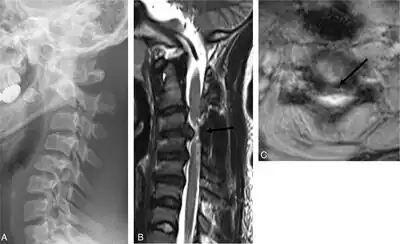

Neuroimaging

Magnetic resonance imaging (MRI) is used to detect morphological brain abnormalities associated with ADCP in patients that are either at risk for ADCP or have shown symptoms thereof.[4] The abnormalities chiefly associated with ADCP are lesions that appear in the basal ganglia.[4] The severity of the disease is proportional to the severity and extent of these abnormalities, and is typically greater when additional lesions appear elsewhere in the deep grey matter or white matter.[4] MRI also has the ability to detect brain malformation, periventricular leukomalacia (PVL), and areas affected by hypoxia-ischemia, all of which may play a role in the development of ADCP.[2] The MRI detection rate for ADCP is approximately 54.5%, however this statistic varies depending on the patient's age and the cause of the disease and has been reported to be significantly higher.[1]